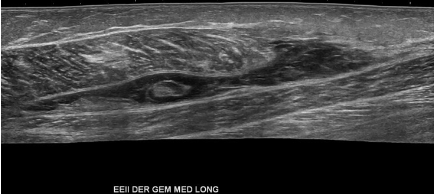

Incidentalmente, extenso desgarro miofascial total del gastrocnemio medial asociado a gran hematoma organizado interfascial. Desgarro miofascial del musculo gastrocnemio lateral.

De forma incidental se observa interrupción fibrilar miotendinosa del musculo gastrocnemio medial asociado hematoma secundario parcialmente organizado.

Desgarro miofascial asociado a hematoma parcialmente organizado del músculo gastrocnemio medial. Se sugiere complementar con estudio dirigido.